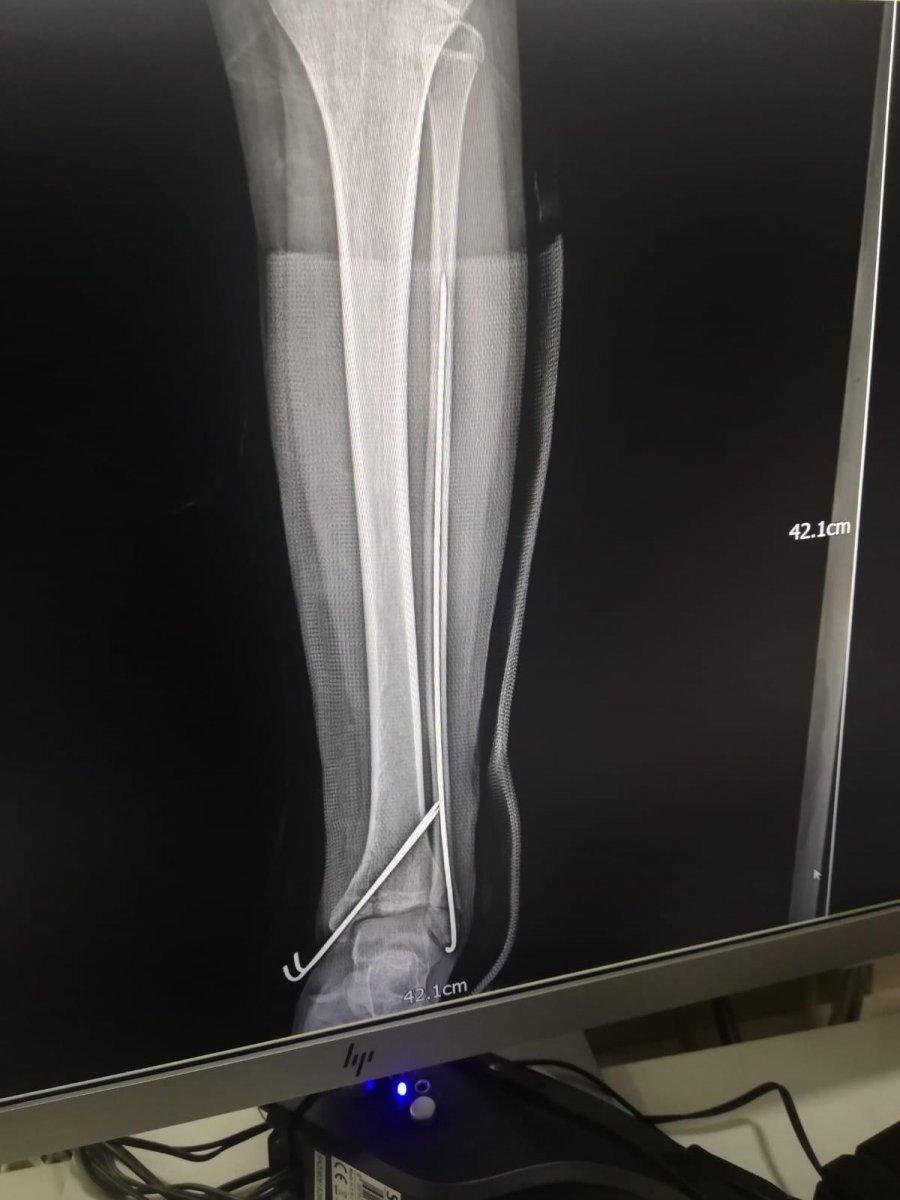

Burada ilk tedavisi yapılan küçük kızın sol bacak ve kolu ile kalça ve kuyruk kemiğinin kırıldığı tespit edilmiş ve Bezmialem Vakıf Üniversitesi Hastanesi'ne kaldırılarak tedavi altına alınmıştı. 9 ay geçen olayın sonrasında Elif Koşucu’nun düşmeye bağlı olarak topallayarak yürüyebildiği, sol koluna platin takıldığı ve sol ayak bilekliğine de yürüyebilmesi için özel bir apart takıldığı öğrenildi.